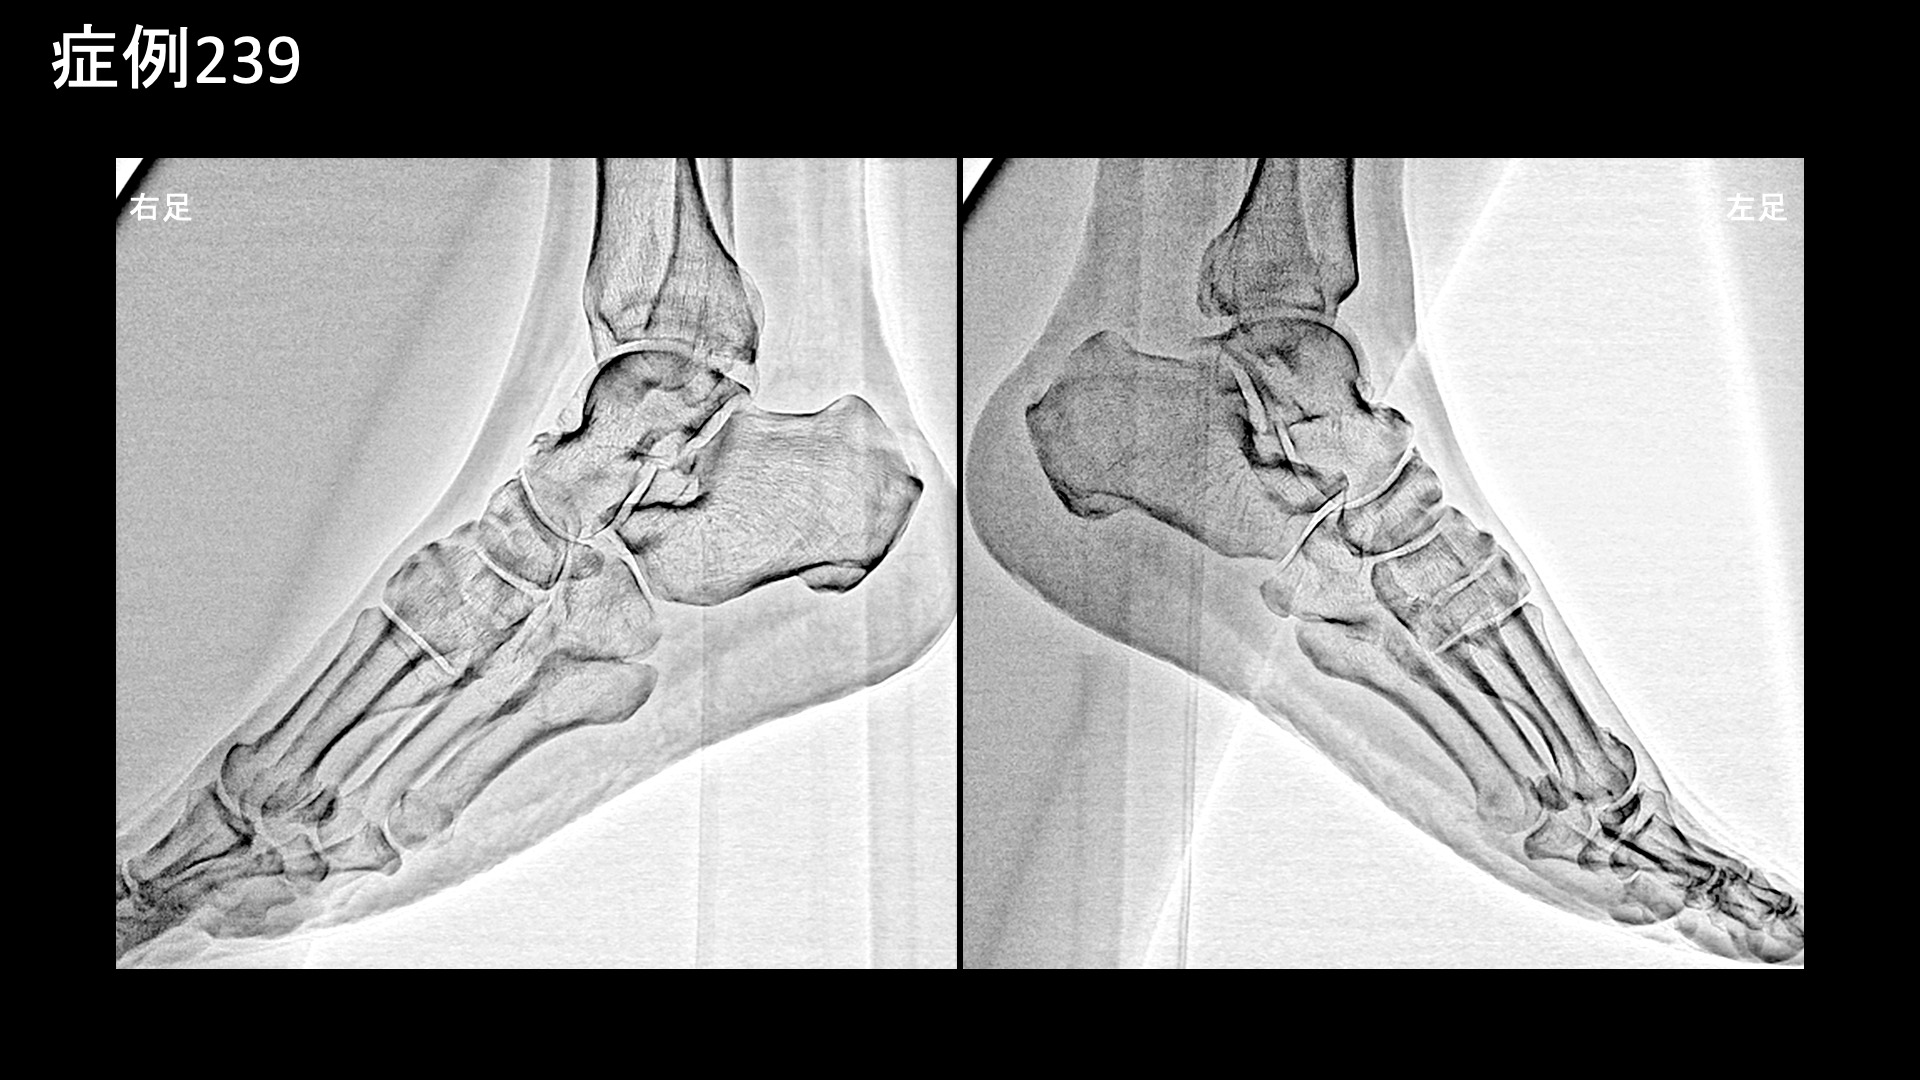

膝:変形性膝関節症など 【70代:男性】夜間痛がその日のうちに改善!強い炎症を伴った変形性膝関節症に対する運動器カテーテル治療(変形性膝関節症) 2025.09.23 鴨井院長による動画解説 受診までの経過 半年前から右膝が痛むようになりました。夜間に疼くようにもなったため、当院を受診しました。 診察時の所見 レントゲンでは両膝関節に中等度以下の変形が見られました(KL分類2/4程度)。両足は扁平足でした。エコーでも同様に中等度までの変形にとどまっていましたが、一方で、異常血流信号は非常に旺盛にみられ、強い炎症が示唆されました。 良い治療適応と判断し、モヤモヤ血管(病的新生血管)に対する運動器カテーテル治療(微細動脈塞栓術)を受けていただきました。 治療の所見 血管造影を行うと、左右とも全周性にモヤモヤ血管が濃染像として描出されました(写真は、下行膝動脈、内側下膝動脈、外側下膝動脈の各血管造影について掲載)。やはり、強い炎症を反映した所見でした。治療後は画像上速やかに消失しました。 治療後の経過 治療直後から症状が改善し、ほぼ痛みが無くなりました。帰り道にも既に違いを実感し、その日の夜にはいつもじんじんと疼いていた痛みが無くなっていました。治療後1ヶ月の再診時には、奇跡的に良くなっている、こんなにも良くなるものかと驚かれました。これまでと人生観が変わり、何か新しいことを初めてみようかと思えるようになったと言われました。その後も違和感を生じることはあるものの、痛みが再燃することはありませんでした。治療後3ヶ月でも順調に経過されており、終診としました。 通常の変形性膝関節症ではもう少し時間をかけて改善することが多いのですが、非常に早期から改善しました。モヤモヤ血管(病的新生血管)に対する運動器カテーテル治療(微細動脈塞栓術)は、炎症が強いほど早期から改善が得られる傾向がありますが、まさにそうした症例でした(夜間痛も強い炎症を反映した臨床所見の一つです)。まだ変形が高度に進行していない内に治療を受けていただけたことも、良い結果が得られた要因です。カテーテル治療の強みを最大限に生かすためには、高度の変形にまで進行する前にご検討いただくとよいと思います。 膝の痛みについては、何とか歩けるうちは医療機関を受診しないという方も多く、受診を決断した時には既に変形が高度に進行していたということも少なくありません。変形性関節症は進行性の病気であり、加齢によっても進行しますが、進行するほど種々の治療が効きにくくなってしまいます。ある程度までの状態でしっかりと治し、その後の進行を予防するための靴・インソール調整、筋力トレーニングなどに取り組み、日常生活についても指導を受けた方が、結果的には長く自分の足で健康に歩くことができますので早めに対処していただくことをおすすめします。昨今では、レントゲンに加えてMRI検査まで受けずともエコー検査である程度の詳細な状態を把握することができますし、そうした医療機関が増えてきています。エコー検査は気軽に受けられますので、状態に応じて、時々チェックを受けるのも良いと思います。 変形性膝関節症の詳しい病状説明はこちら 【80代:女性】新型コロナウイルス感染を契機に悪化した変形性腰椎症による腰痛/坐骨神経痛(新型コロナウイルス感染、変形性腰椎症、腰痛、坐骨神経痛) 前の記事 【10代:男性】恥骨が痛くて走れない、スポーツが原因で生じた恥骨結合炎に対するモヤモヤ血管治療(恥骨結合炎) 次の記事